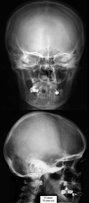

RTG głowy 10-letniego dziecka..

. RTG głowy dziecka w okresie

od 2 do 10 roku.

RTG głowy frontalny.

RTG głowy boczny.